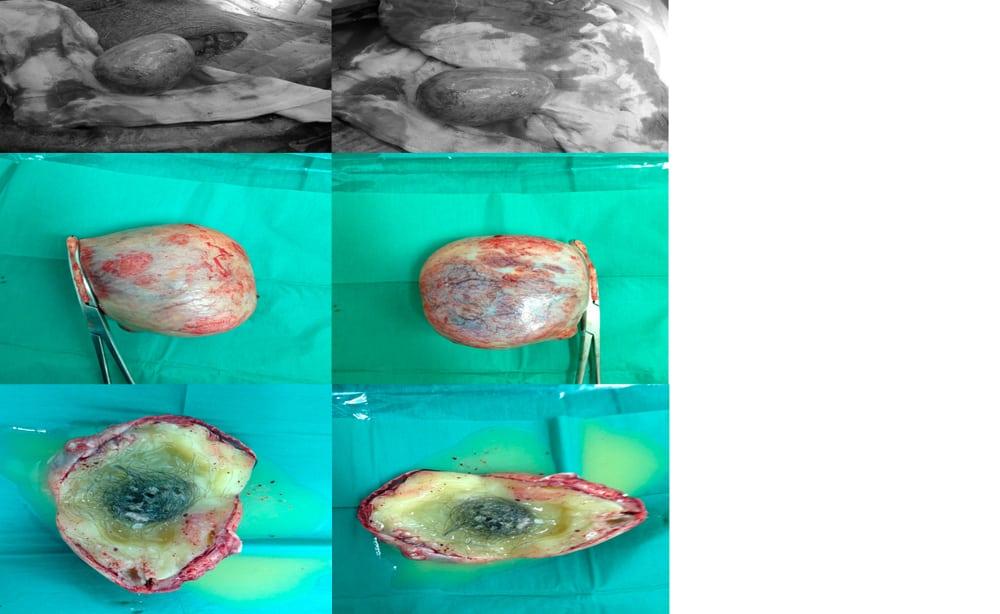

ဒီတစ်ခါတော့ လူပြုစားတာတဲ့။ ခွေးတွေ၊ကြောင်တွေရဲ့အမွေးတွေစုပြီး ပိတ်ခဲနေတာတဲ့။ ဒီလိုအရပ်ပြောစကားတွေနဲ့ အရည်အိတ်ပြဿနာဟာ ဆရာဝန်တွေရဲ့ ခွဲစိတ်ကုသမှုနဲ့ ခွဲထုတ်လိုက်တဲ့အရည်အိတ်ထဲမှာ အမွေးလိုလို ဆံပင်လိုလိုတွေ ပါနေတဲ့အကြောင်းနဲ့ လူမှုမီဒီယာမှာပျံ့နှံ့လာပါတယ်။

ဒါတွေ ဟုတ်မဟုတ်ကို ဆေးပညာအရ အဖြေရှာကြည့်ရင် Dermoid Cyst လို့ခေါ်တဲ့ အရည်အိတ် က အဓိကတရားခံပါ။ Dermoid Cyst ထဲမှာ အမွေး၊ အရည်၊ သွား၊ အရေပြားဂလင်းတွေ‌ပါဝင်နေတတ်ပြီး ခန္ဓာကိုယ် တစ်နေရာရာမှာ ဖြစ်လာတတ်ပါတယ်။

မွေးတည်းက ပါလာတတ်ပြီး မသိသာပေမယ့် နည်းနည်းချင်းပဲ ကြီးထွားလာတတ်တဲ့ အရည်အိတ်ပါ။ မျိုးပွားဆဲလ်တွေကနေဖြစ်လာတာမို့ အမွေး၊ အဆီ၊ သွား၊ အရိုး၊ ချွေးဂလင်းတွေရဲ့တစ်ရှူးတွေ ပါဝင်နေတာပါ။